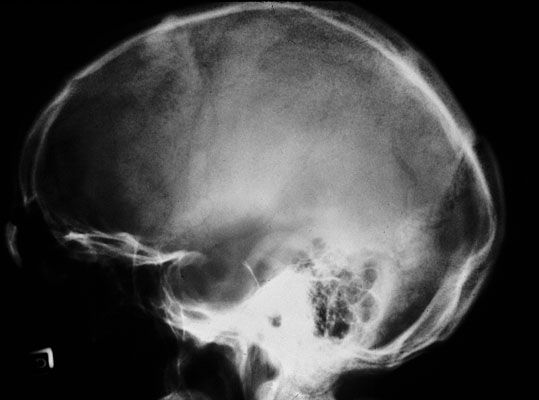

Effects of pituitary macroadenoma, skull film

Similar case in vivo: Plain film (sagittal view) of skull shows ballooning of sella.